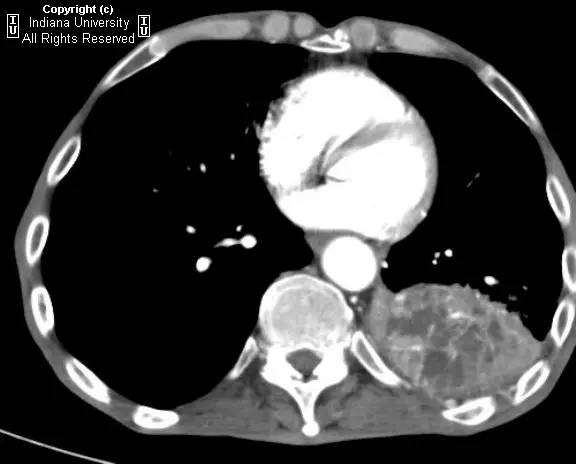

【病史】男性,咳嗽,体重减轻。

胸片示肺内高度膨胀性病变,膈肌扁平。左后胸部可见较大卵圆形不透亮区并液平面。CT示左肺下叶近后胸壁较大厚壁肿块并部分空洞形成,实性部分不均质强化。右肺下叶可见分叶状结节。左前下少量气胸。

【诊断】鳞状细胞肺癌并后部阻塞性肺炎